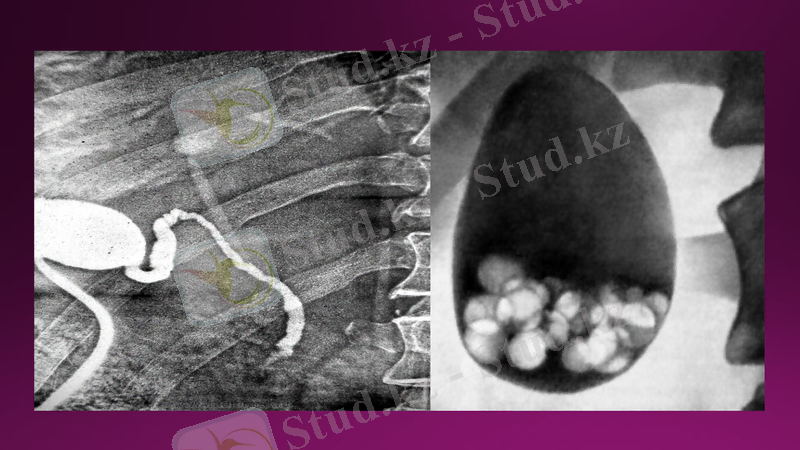

Бауыр ангиографиясы іш қолқасының висцералды бұтақтарын селективті ангиографияны енгізумен үлкен клиникалық мәнге ие болды. Ангиографиялық әдістер арасында целиако - және мезентерикография кеңінен таралған. Ангиографияны патологиялық процесті анықтау және оның ерекшеліктерін анықтау үшін, сондай-ақ жедел емдеу мәселесін шешу үшін қолданады. Бұл әдіс бауырдың ошақтық зақымдануын, ісіктерді, паразиттік ауруларды, даму ақауларын және осы аймақтағы өз тамырлы патологиясын анықтау үшін қолданылады. Әдіс пациенттің ауыр жағдайы, жіті жұқпалы аурулар, психикалық бұзылулар, йодты препараттарға жоғары сезімталдық кезінде қолдануға болмайды

Бауыр ангиографиясы

Сонымен қатар, клиникалық практикада гепатовенография (бауыр флебографиясы) қолданылады. Әдіс бауыр циррозы бар емделушілерде шунт салу операциясының алдында бауырдан кету жағдайын нақтылау, Бадц-Киари синдромын диагностикалау қолданылады.

Гепатовенография

Холецистография өт қабы мен өт жолдарының анатомиялық құрылымы мен функционалдық белсенділігін зерттеу үшін тағайындалады. Алынған бейнеде зерттелетін аймақтың пішіні мен жағдайын, нормадан ауытқыған оның жағдайының жылжуын бағалауға болады. Жаңа түзілімдер мен тастардың шамасы әртүрлі жазықтықтарда жасалған бірнеше суреттер бойынша бағаланады. Екі өлшемді сурет өт қабының немесе түтіктердің жұмысына кедергі болатын көлемді аномальды түзілімдерді, ісіктерді және полиптерді бағалауға мүмкіндік береді. ішкі органның айқын суретін береді: өт қабы тегіс пішінді және жұқа пішінді алмұрт тәрізді пішінді болады. Нормадан кез келген ауытқуларды дәрігер-рентгенолог бекітеді және зерттеудің қосымша әдістерін тағайындау үшін себеп болып табылады. Өт қабының пішіні дененің құрылымдық ерекшеліктеріне байланысты нормадан өзгеше болуы мүмкін. Гиперсстениктерде көпіршік дөңгелек формамен ерекшеленеді, ал астеникте жоғары созылған: орган құрылымы мен орналасуының ерекшеліктерін бойынша қорытынды жазатын дәрігер бағалайды.